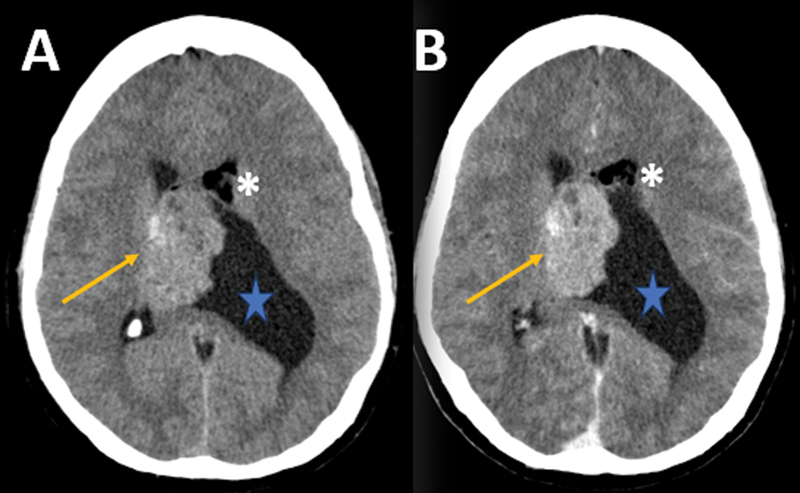

Lateral ventricle central neurocytoma with lipidization: a case report of an underrecognized presentation.

侧脑室中枢神经细胞瘤伴脂化:一例未被充分认识的表现。